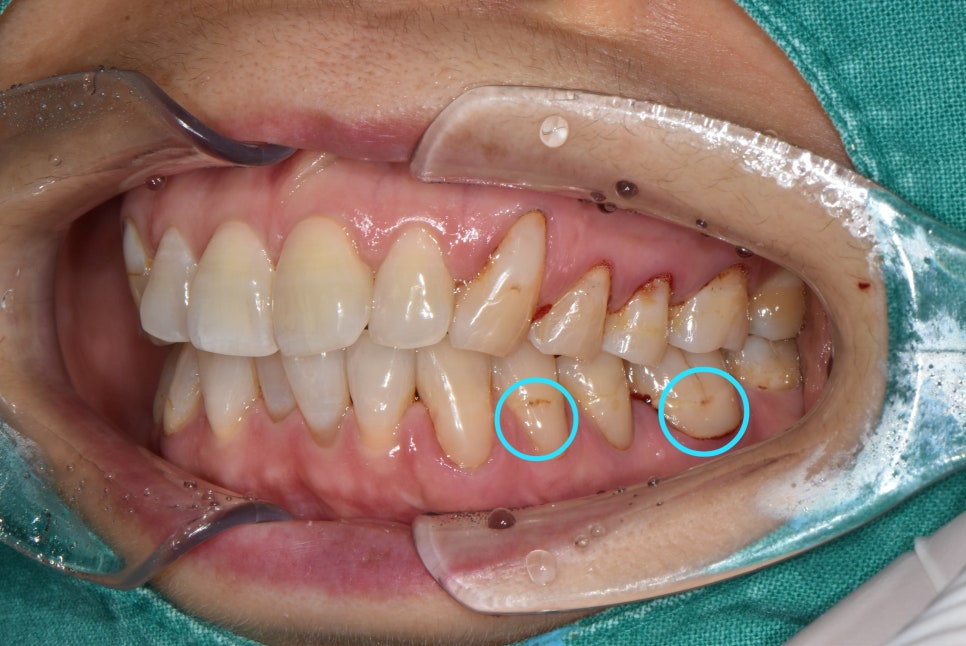

안녕하세요. 의정부 <바른손 치과>입니다. 오늘은 착색 제거에 대해서 설명드리고 보여드리려합니다. 착색 제거는 미백치료를 해야만 한다고 생각하실 수 있는데요. 치아 전체를 미백하지 않고 부분적으로 착색된 치아들만 깨끗하게 하실 수도 있습니다. 미백을 하지 않았지만 착색 제거만으로 치아를 깨끗하게 해드렸던 케이스를 보여드릴게요! 전체적인 검진과 스케일링을 하러 오셨던 환자분입니다. 치아를 확인해보니 치경부 마모증으로 인해 레진치료를 하셨고 레진 충전물과 치아의 경계부에 착색이 되어있으셨습니다. 이런 충전물을 다 떼어낸 후 다시 하기에는 너무 아깝잖아요? 시간도 들고.. 비용도 들고.. 그렇기 때문에 기존 충전물을 더 오래 사용하실 수 있도록 레진 착색제거를 시행하였습니다! 충전물 연마로 착색 제거를 한 후 사진입니다. 더 비교하기 쉽게 사진을 보여드릴게요! 동일 부위 비교 사진을 보시면 확실히 연마 전 사진보다 환하고 깨끗해진 치아가 된게 보이시나요?? 간단하게 다듬기만 했을 뿐인데 더 건강한 치아처럼 보이네요 ㅎㅎ 충전물을 새로 안 해도 되고 너무 깔끔해졌다고 환자분도 만족 하셨답니다! 이렇게 깨끗하게 만든 치아를 다시 착색되도록 할 순 없겠죠!? 치아가 착색되지 않게 하려면, 흡연이나 커피, 홍차, 와인, 카레와 같은 음식들을 되도록 피해주시고 식사 후 바로 양치질 하시는 습관이 제일 좋습니다. 오늘은 이렇게 치아 착색 제거 케이스를 보셨는데요. 다음번에 더 유익하고 좋은 정보를 가지고 오겠습니다ㅎ 환자분의 심미적인 치아를 생각하는 의정부 <바른손 치과>였습니다. 감사합니다! |